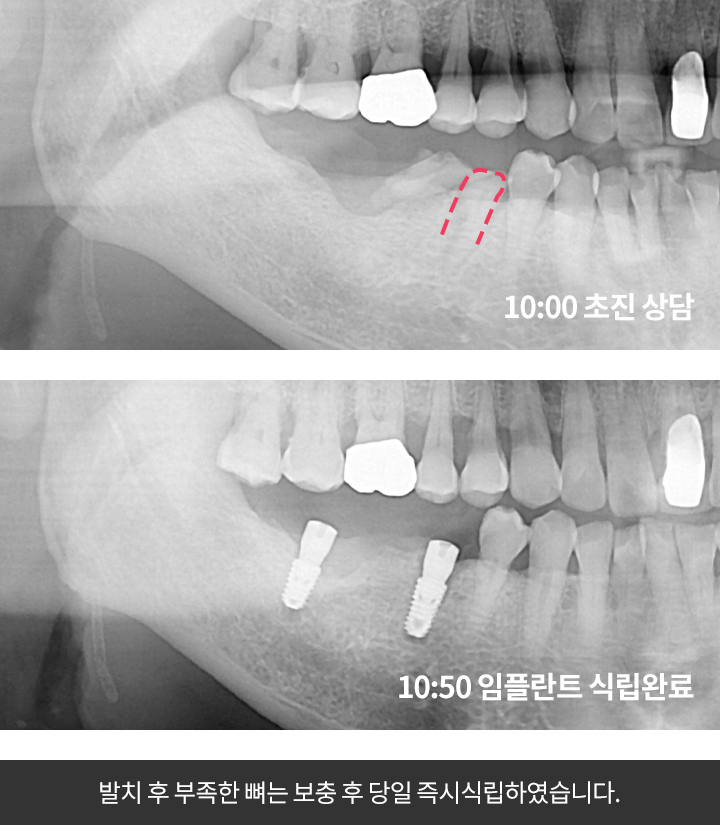

발치해야하는치아를 뽑은 직후 필요시 잇몸뼈까지 이식 후 임플란트를 식립하는 방법입니다.

발치를 한 즉시 임플란트 픽스쳐를 식립하기 때문에

발치 후 회복을 거쳐야하는 기존의 임플란트 방식보다 빠르고 안정적입니다.